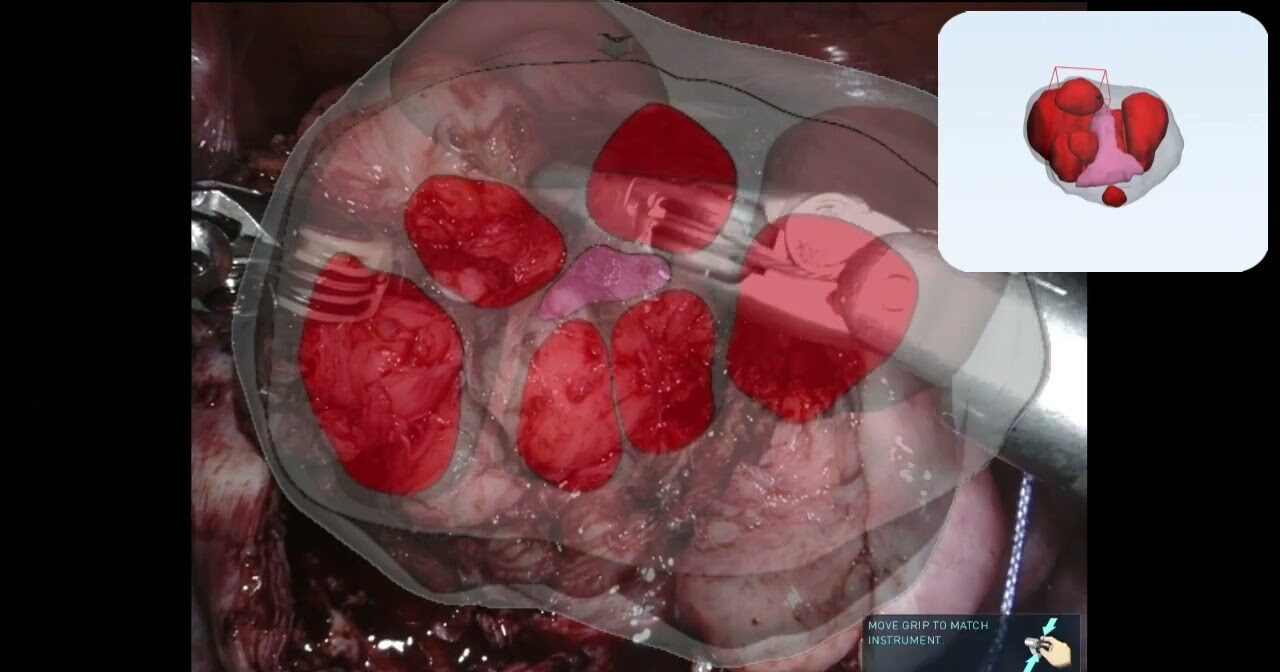

#332 First-in-man AI-assisted Augmented Reality Surgery Drs. Alex Mottrie & Jasper Hofman

PSMA Radio Guided Surgery in Primary Prostate Cancer

Robot-assisted radioguided surgery using a DROP-IN gamma probe